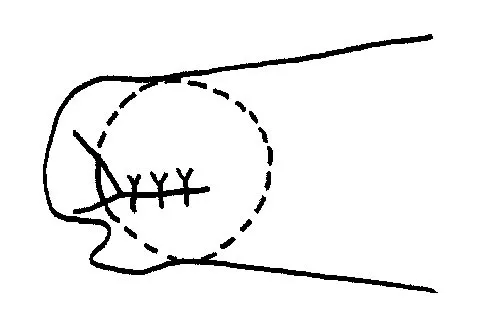

Initial repair of the large U-shaped rotator cuff tear shown in Figure 12 consists of closing the tear side-to-side to take advantage of margin convergence. The most significant biomechanical consequence of this repair step results in

Explanation